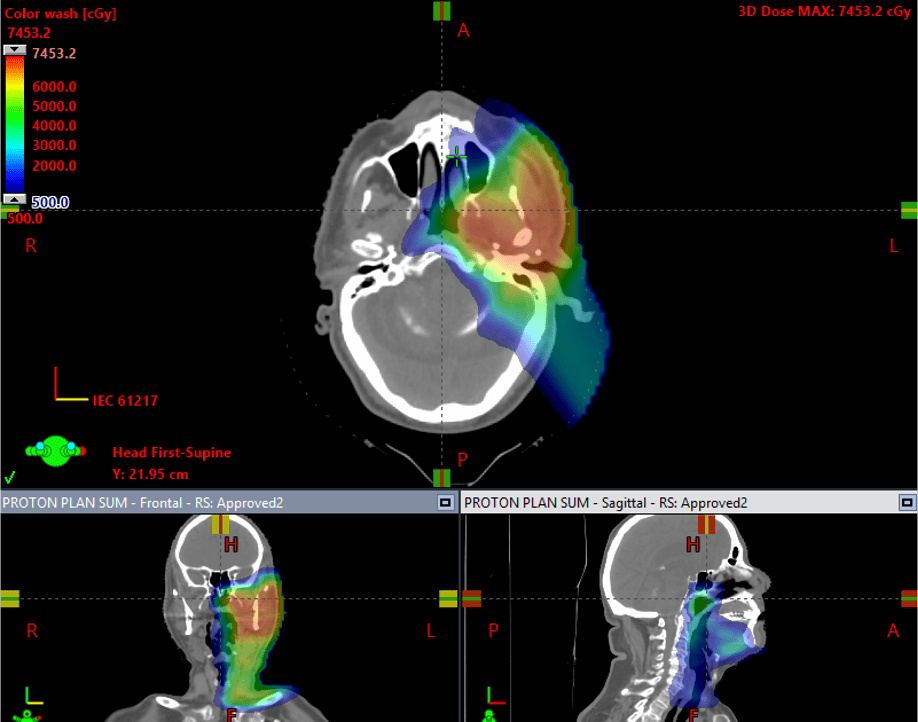

Proton therapy

Proton therapy is especially useful if only treating one side of the neck. This is safely done in well-lateralized tonsil tumors or salivary gland tumors. The advantage of protons over X rays is the intermediate and low dose radiation to the uninvolved side can be negligible. A randomized trial comparing IMRT to proton therapy in head and neck cancers was recently presented at ASCO 2024, showing equivalent tumor control but less swallowing toxicity with protons. The closest proton centers to Reno are in southern California or Seattle due to the expense of building these cyclotrons.